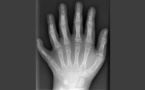

Tags (3) : doigts